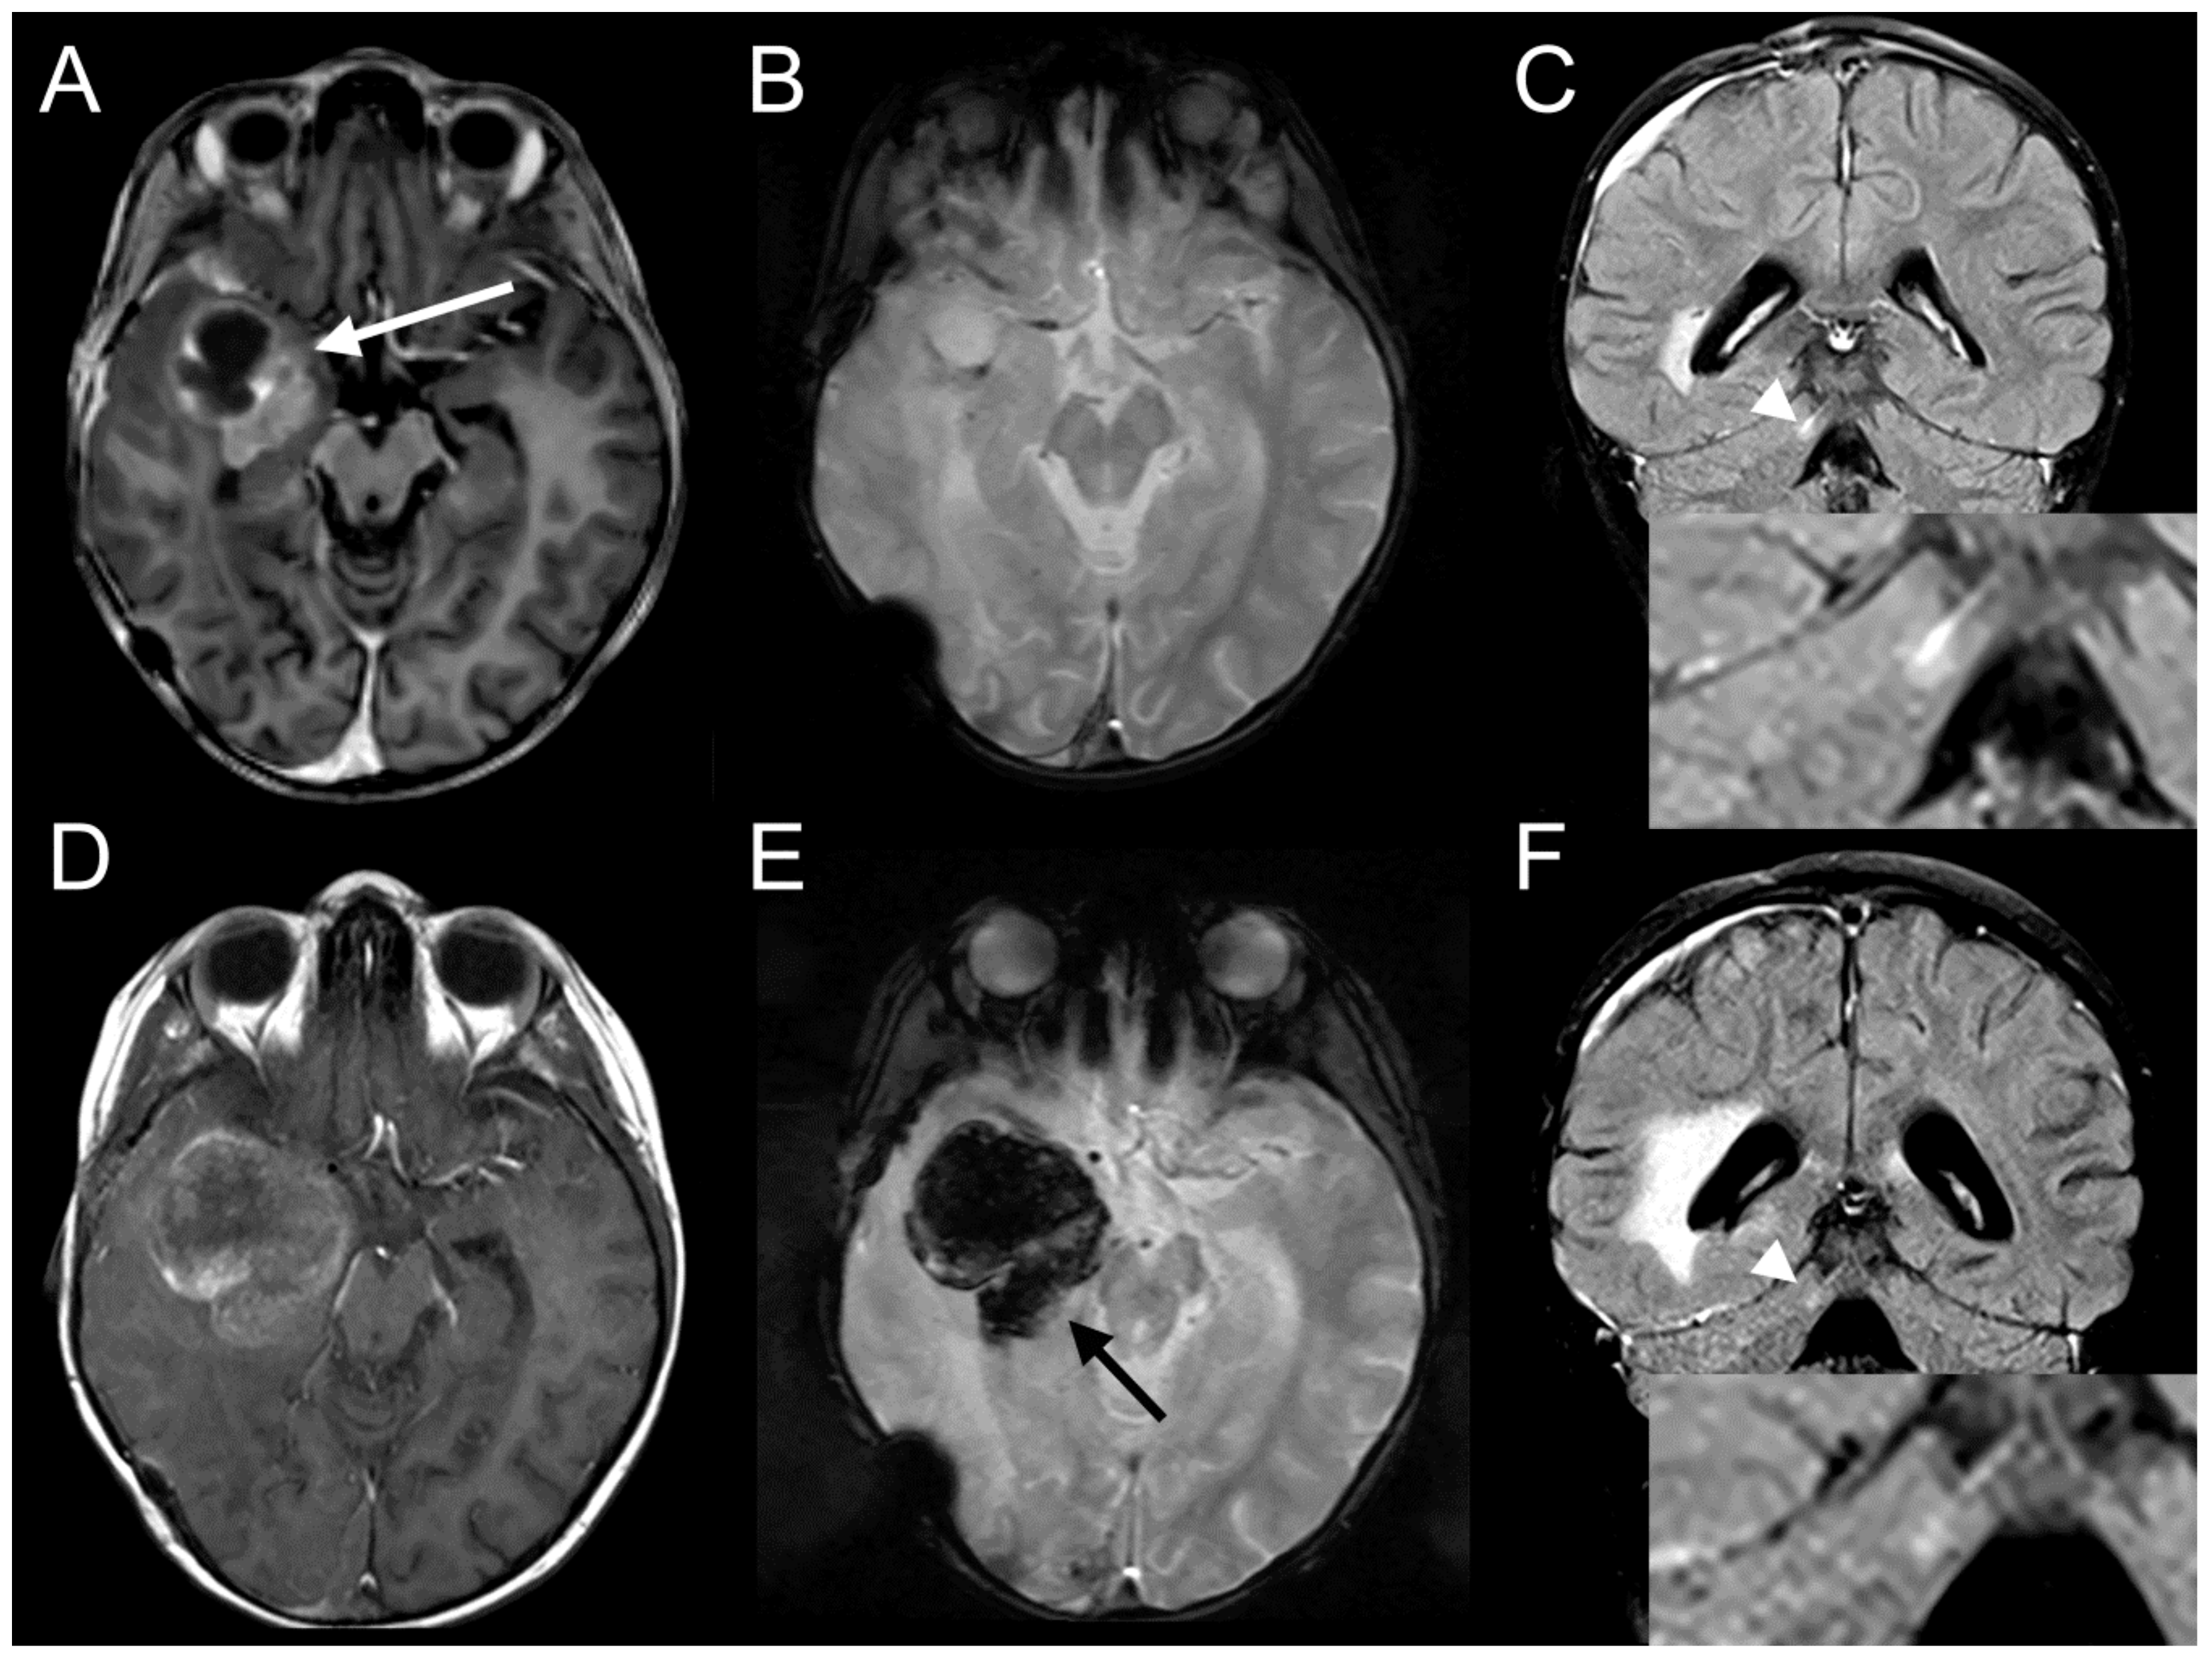

2.7. Ceritinib Induces Tumor Regression in Vivo